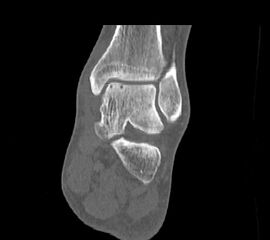

Die Kombination von SPECT und CT in einem Untersuchungsgang bringt wie bereits oben erwähnt eine erhöhte Ortsauflösung und artefaktfreie Darstellung von Knochenstoffwechselveränderungen der SPECT bei gleichzeitig excellent guter anatomischer Darstellung/Zuordnung durch die CT 3. Auf die Vorteile der CT gegenüber dem konventionellen Röntgen muss nicht mehr besonders eingegangen werden. Besonders eignet sich die „SPECT-CT“ zur Diagnostik von Fußerkrankungen (Biersack HJ et al. 2012).